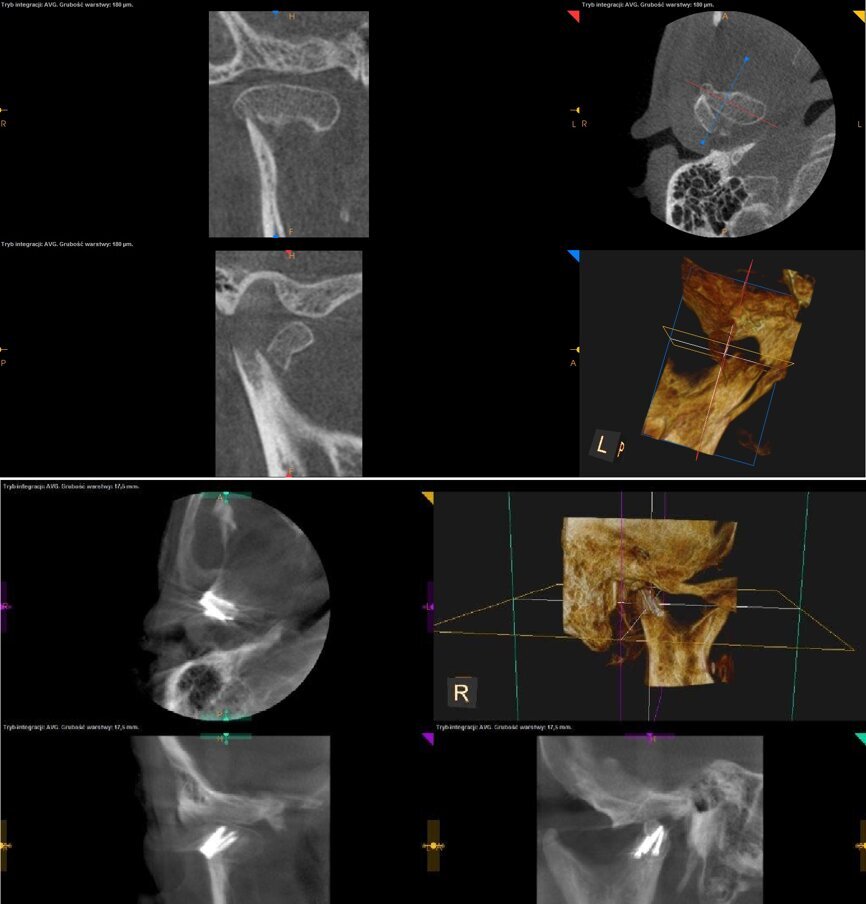

Przeprowadzono pełną diagnostykę. Wykonano liczne badania dodatkowe w postaci pantomografii, tomografii stożkowej o zmiennym polu obrazowania oraz badanie przy pomocy T-scan V, tj. elektronicznej kalki do sprawdzenia warunków okluzyjnych. Badanie tomograficzne wykonano za pomocą aparatu Carestream 9300 (Carestream Dental), wykorzystując obrazowanie 8/8, ukazujące badany region żuchwy – gałąź wraz z jej trzonem oraz staw skroniowo-żuchwowy.

Zdjęcie panoramiczne w tym przypadku nie stanowiło jednoznacznej metody diagnostycznej. Dopiero, porównując zdjęcie po urazie ze zdjęciem wykonanym przed urazem, widoczne było skrócenie gałęzi żuchwy po stronie prawej. Dzięki wykorzystaniu przekrojów osiowych i transsektalnych w badaniu tomografem stożkowym o zmiennym polu obrazowania ustalono przyczynę zaburzeń okluzji u pacjenta oraz w sposób jednoznaczny określono uszkodzenie w obrębie stawu skroniowo-żuchwowego. Po analizie zdjęcia tomograficznego zdiagnozowano u pacjenta złamanie wyrostka kłykciowego żuchwy po stronie prawej. Co istotne, diagnostyka przeprowadzona na podstawie zdjęcia pantomograficznego nie dawało tak ewidentnego wyniku, jak obrazowanie stawu skroniowo-żuchwowego z wykorzystaniem obrazowania 3D. Bez porównania zdjęcia panoramicznego przed i po urazie dostrzeżenie nieprawidłowości było trudne dla niedoświadczonego lekarza.

Ryc. 1_ Okna obrazowania w tomografii stożkowej o zmiennym polu obrazowania.